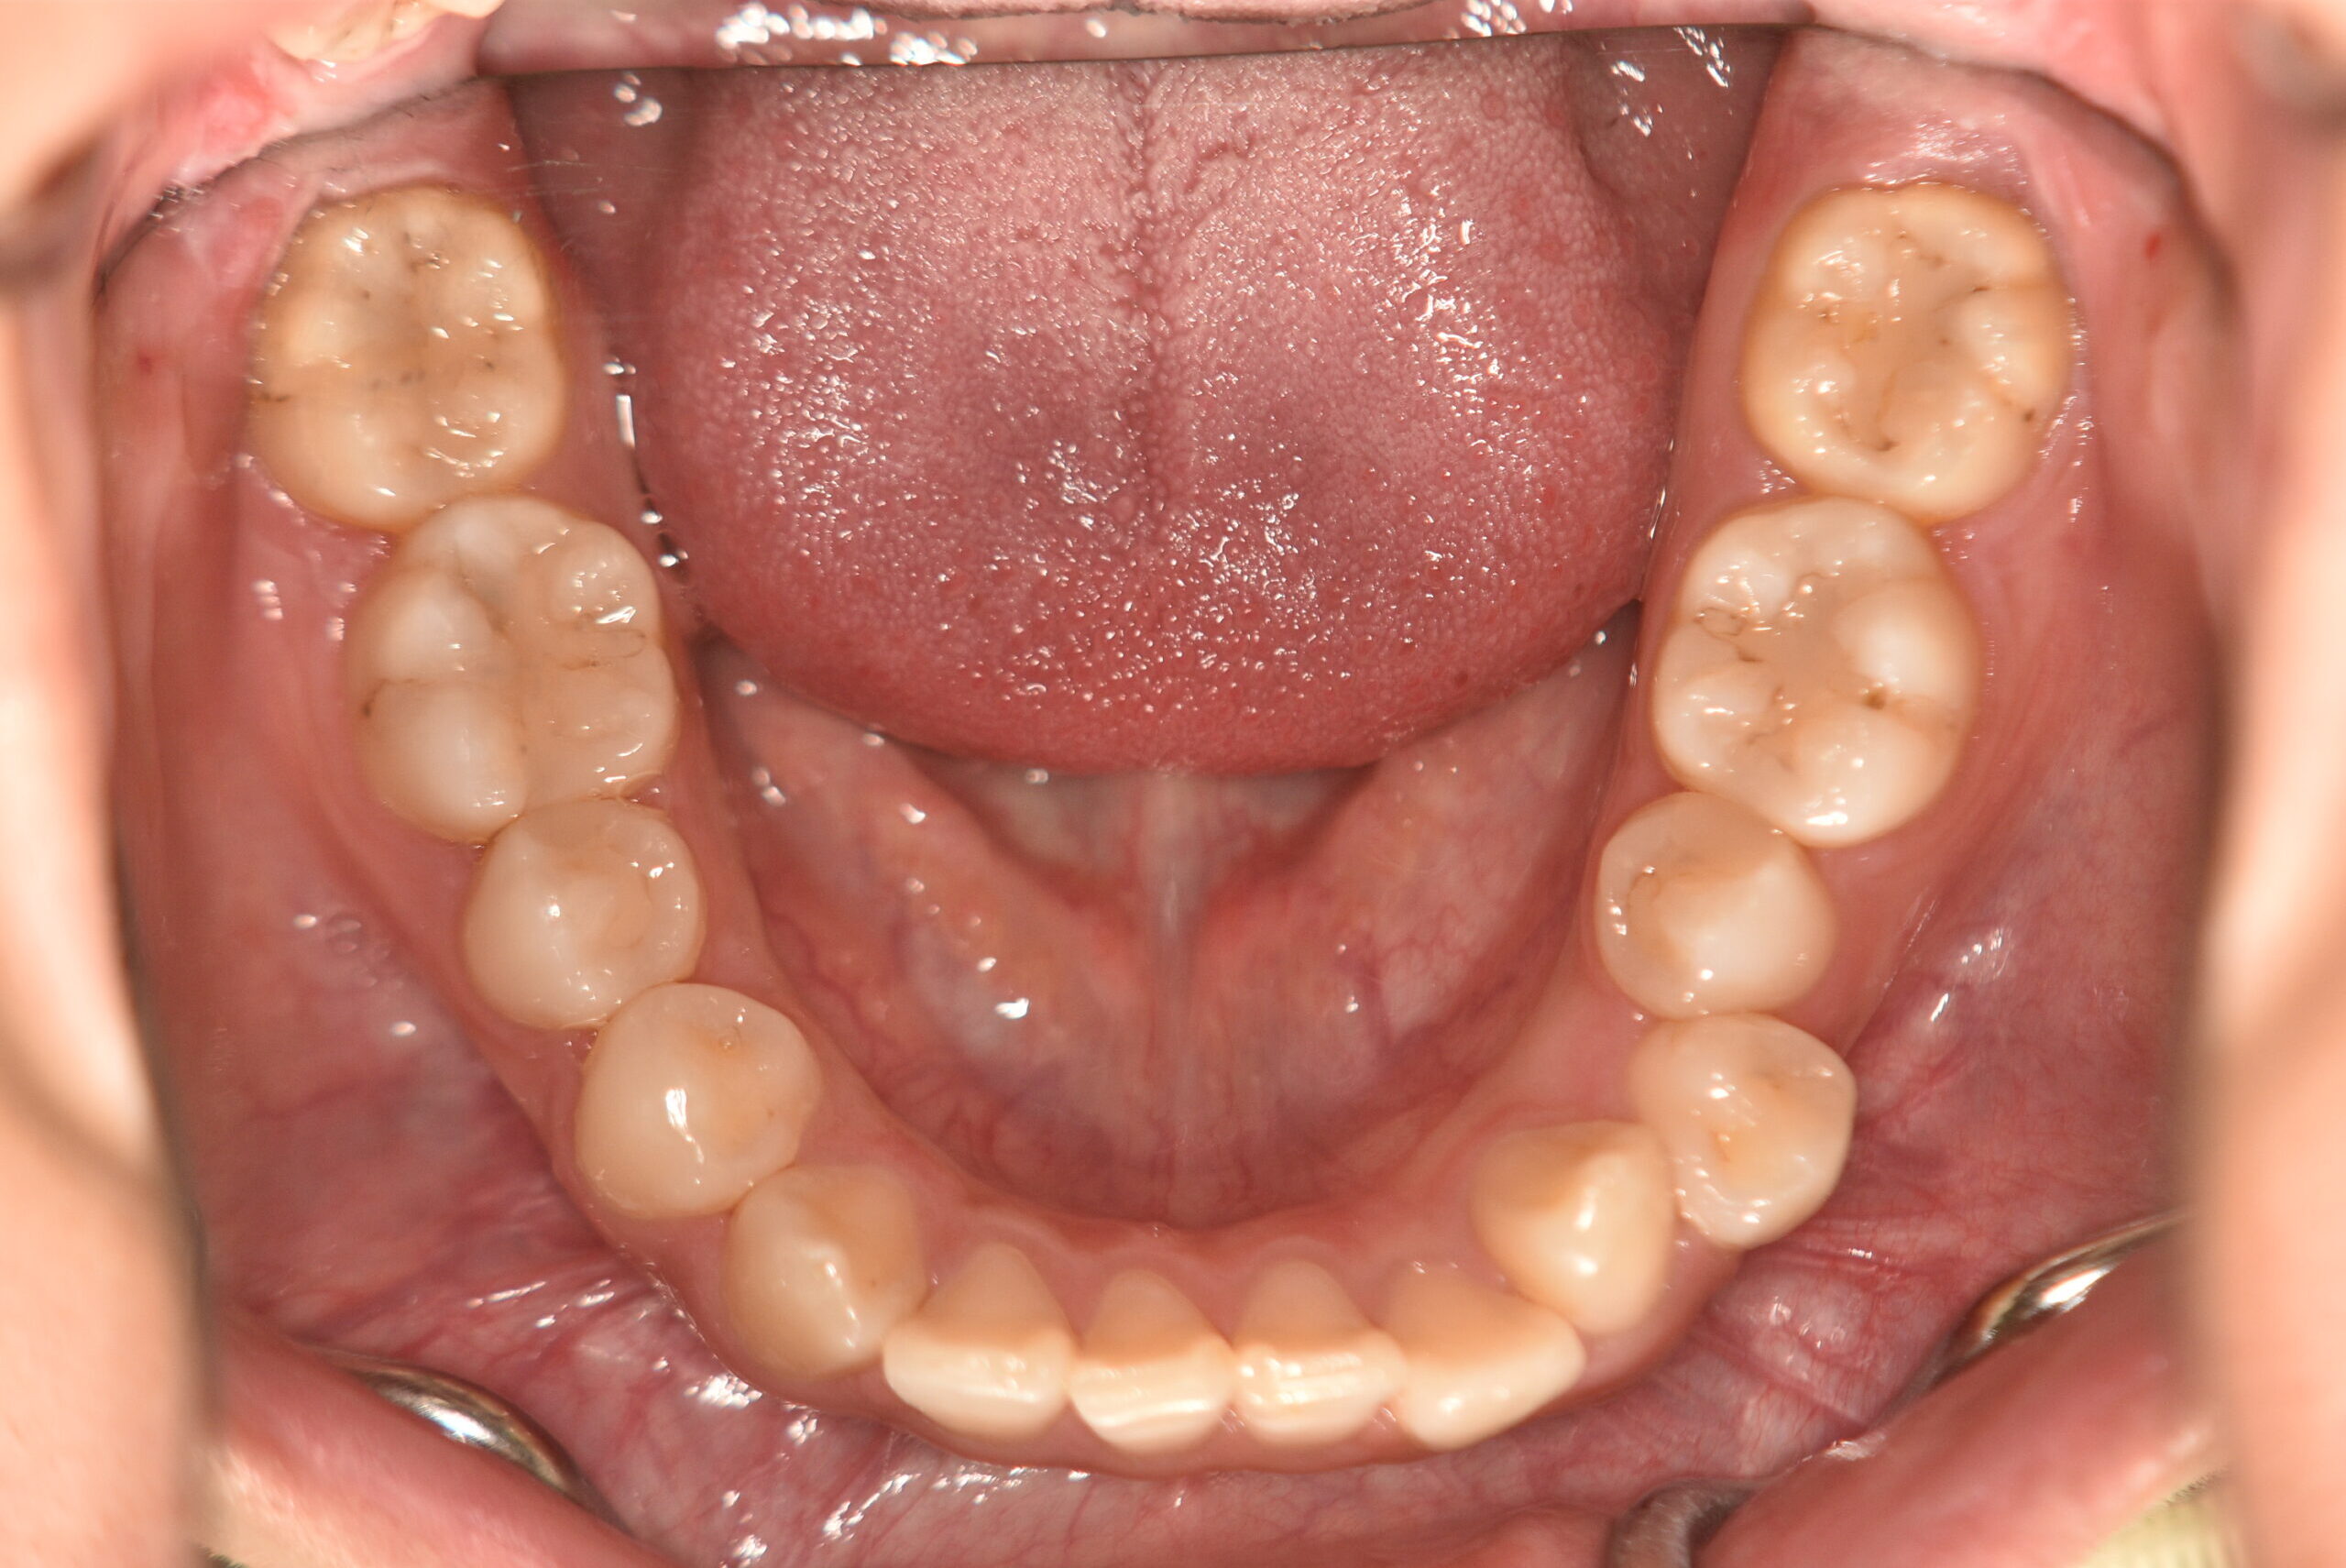

| 治療内容の詳細 | 初診時19歳の女性で、歯のがたつき、かみ合わせを気にされ来院されました。 検査の結果、上顎前歯部叢生を伴うアングルⅡ級1類不正咬合と診断しました。 治療としては、非抜歯の上、セルフライゲーション装置(デーモンシステム)で配列を行いました。 同時に顎間ゴムにて咬合関係の改善を行いました。 治療期間は、2年2ヶ月でした。 |